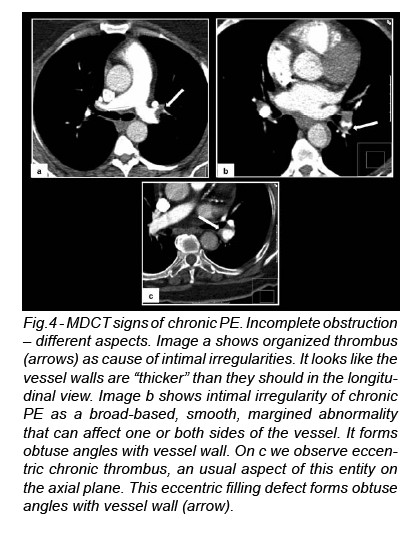

Direct signs of chronic Pe (3-5)

Nonobstructive Filling Defects

The organized thrombus of chronic PE can cause intimal irregularities, bands and webs, and abrupt vessel narrowing; any of these can lead to a pulmonary artery stenosis.

Intimal Irregularities

Intimal irregularities are broad-based, smooth, margined abnormalities that create obtuse angles with the vessel wall.They may beunilateral or bilateral. Pulmonary artery intimal irregularities can also be due to plaques secondary to pulmonary hypertension (Fig.4).